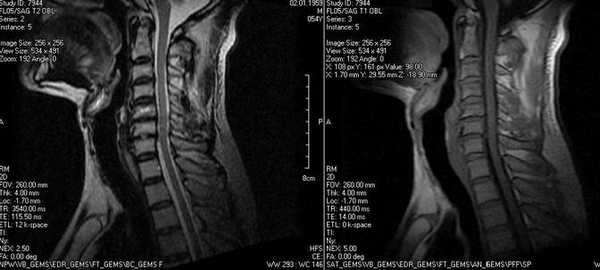

Результат МР-сканирования мягких тканей шеи

МРТ мягких тканей шеи